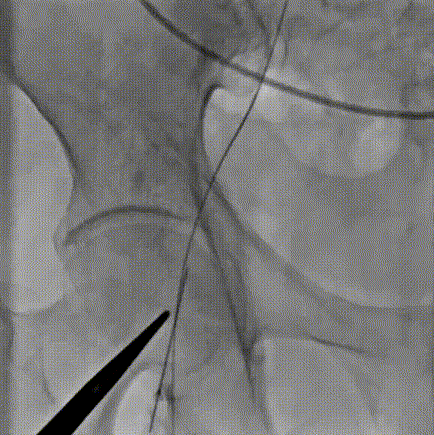

1.以左侧股动脉为辅路,造影指导下穿刺右侧股动脉为主入路;

2.主动脉根部造影,可见瓣口开阖运动差,并存在中量返流,主动脉及心脏受高速血流冲击,位移幅度较大;

3. 直头导丝跨瓣,通过交换导丝将猪尾导管引入左室,测得平均跨瓣压差约60mmHg;